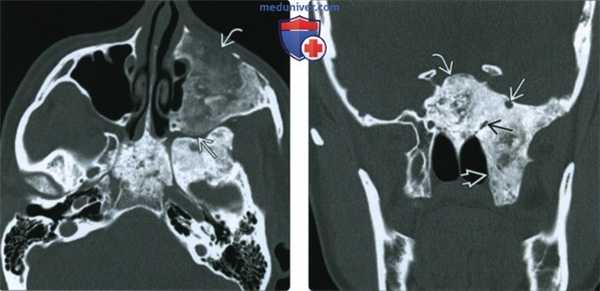

(Слева) При КТ в костном окне в аксиальной проекции отмечаются утолщение, склероз и изменения типа матового стекла левого большого крыла клиновидной кости. Обратите внимание на левый клиновидно-височный шов, резко разграничивающий нормальную кость и зону патологических изменений; такая картина типична для фиброзной дисплазии.

(Справа) При аксиальной MPT Т2ВИ FS у этого же пациента в зоне патологических изменений кости регистрируется преимущественно гипоинтенсивный сигнал. При МРТ отмечается высокая вариабельность МР-сигнала и характера контрастирования пораженной кости, зависящих от соотношения фиброзной и склеротической тканей.

(Слева) КТ, костное окно, аксиальный срез: у девятилетней пациентки наблюдается кистозный вариант фиброзной диспла -зии. Обратите внимание на зоны явной кистозной трансформации в области более характерных изменений по типу «матового стекла» и в смежных с ними отделах.

(Справа) КТ, костный режим, корональный срез: у этой же пациентки определяется экспансивная фиброзная дисплазия (ФД) носорешетчатой области; поражения имеют кистозные структуры, которые характеризуются тонкими, но скперозированными стенками..3. КТ признаки фиброзной дисплазии: